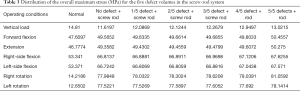

Under each working condition, as the defect volume increased, the stress differences between consecutive groups were as listed in Table 4.

Full table

We used the data to generate a dot plot to more intuitively show the relationship between the defect volume and the increase in stress (Figure 14).

The 5/5 defect in the anterior column of the injured vertebra was a simulated extreme condition that does not exist in actual clinical practice, so we removed this condition from consideration. According to the chart, after the implantation of the internal fixator, the stress increased significantly when the injured vertebra showed a defect. As the defect volume increased, the stress increased correspondingly, and the increase in stress represented by group D (stress difference between the 3/5 defect group and the 4/5 defect group) was the greatest.

From the data analysis of the stress on the screw-rod system, it can be concluded that with the collapse of the superior endplate of the injured vertebra and the gradual increase in the defect volume of the anterior column, the stress gradually concentrated on the internal fixator (Table 5).